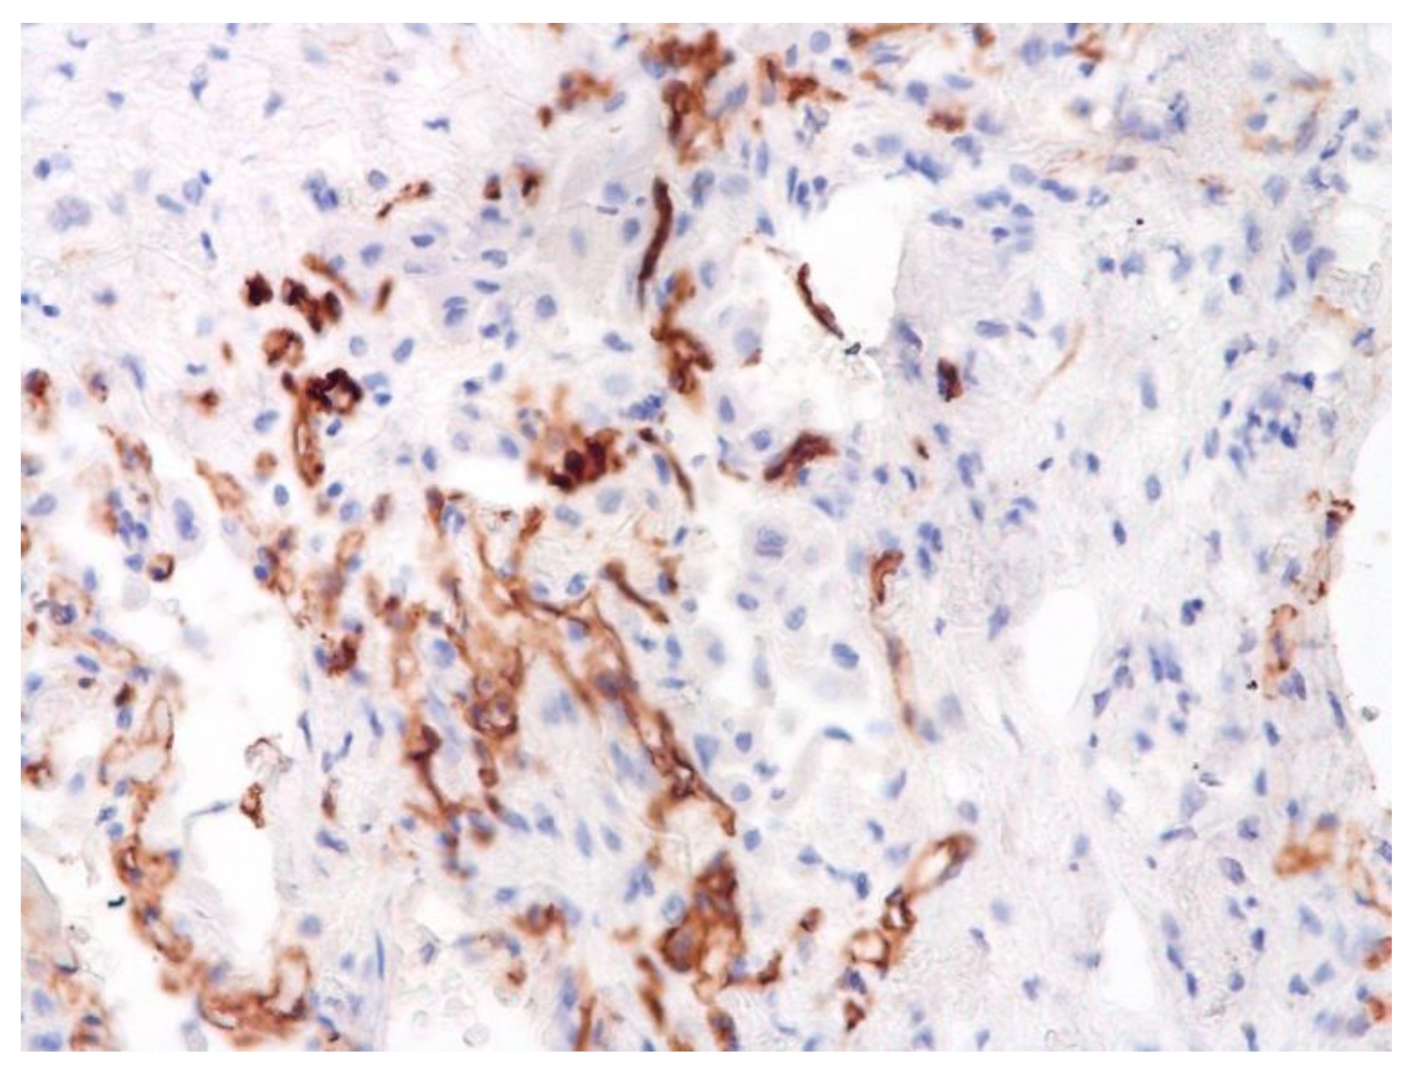

Figure 10.

Numerous CD3+ lymphocytes in lung. IHC ×50.

The dynamics of changes in ARDS associated with COVID-19 can only be judged by analogy with SARS and influenza A/H1N1pdm. In the late (productive) stage (after 7–8 days or more from the onset of the disease) of diffuse alveolar damage, macroscopically the lungs are enlarged, low-air, dense, fleshy, and can resemble the density of the liver, sometimes with diffuse whitish layers and areas of different sizes. Microscopically, siderophages, a relatively (in comparison with swine influenza) small number of hyaline membranes (Figure 9), fibrin, squamous metaplasia of the bronchial, and bronchiolar and alveolar epithelium can be detected in the lumens of the alveoli, respiratory and terminal bronchioles, the thickening of the interalveolar septa due to sclerosis, lymphoid (mostly CD3+ and CD 8+) (Figure 10 and Figure 11) and macrophage (Figure 12) infiltration, and the proliferation of type II alveolocytes. The nature of cytoproliferative changes of the epithelium in the trachea and bronchi remains unclear. In the final stage of the disease, sections of fibrous tissue may develop in all parts of the lungs (usually in the lower lobes) (Figure 13), which contributes to the development of chronic respiratory failure. It is notable that near the overgrowth of collagen fibers in the lungs, neoangiogenesis is also typical (Figure 14). The electron microscopic study revealed changed viral particles (Figure 15).